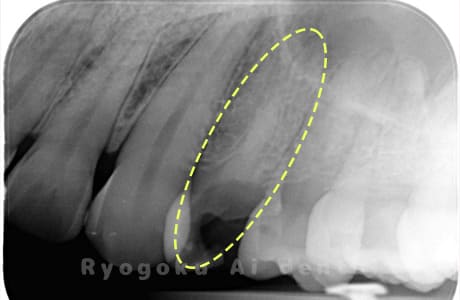

Case02

- 原因

- 慢性根尖性歯周炎

- 治療期間

- 3ヶ月

- 治療内容

- マイクロエンド

- 治療費用

- 121,000円

噛むと痛みが出る、とのことで来院した患者様です。他院での根管治療を終えてましたが、根尖病変を認めるため、マイクロエンドを行いました。

<リスク・副作用>

術後は痛み、腫れ、痺れなどの副作用が生じる場合があります。症状が再発する可能性があります。